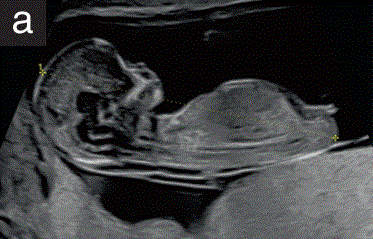

•  头臀长度(CRL)应作为常规孕早期检查的一部分进行测量,无论是经腹还是经阴道(图1-a)。

• 这种测量应该 应按照标准切面进行。

--胎儿在屏幕上的方向是水平的, 胎头和胎臀之间的测量线与超声束的约为成90度角。

--胎儿应处于自然状态(即既不弯曲也不过度伸展)。

--图像应该充分放大,充满超声屏幕的大部分宽度;

--卡尺应放在头冠和臀部的端点,需要清晰地观察;

• CRL的测量应用于估计所有情况下的胎龄,体外受精妊娠除外;

图1 11+0至14+0周胎儿超声检查可获得的测量值。(a)用于评估胎龄 测量胎儿的头臀长度(CRL),以评估胎龄。在测量CRL时,卡尺的位置应对应于从胎儿头顶到臀部的最长直线。